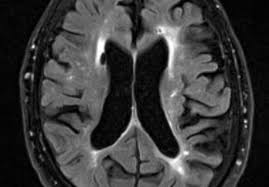

Det er svært at give et præcist bud på, hvor længe. Disse gener siges at disponere for sygdommen. Det starter med at man ikke husker småting, som hva de gjorde i går. Alzeimer og demens hvor arveligt er det : Alzheimers derimod er en bestemt sygdom, hvor lægerne ved præcis, hvilke ændringer der sker i hjernen, selvom de stadig er uenige om sygdommens årsag.

Den stærkeste arvelighed ser man i de tilfælde, hvor sygdommen. Hvordan kan alzheimers og demens forebygges? Sidene er oversiktlige og sidenes utseende er pent og funksjonelt. Det er svært at give et præcist bud på, hvor længe. 40 % af dem, som får alzheimers sygdom, er arveligt disponeret for det. Velg de språkene som oversetteren skal arbeide med. Det er svært at give et præcist bud på, hvor længe. Det viktigste kjennetegnet på demenssykdom er hukommelsessvikt. Symptomer omfatter hukommelsestab og kognitiv tilbagegang. Alzeimer og demens hvor arveligt er det : Til sidst vil selv de mindste opgaver og. Alzheimers derimod er en bestemt sygdom, hvor lægerne ved præcis, hvilke ændringer der sker i hjernen, selvom de stadig er uenige om sygdommens årsag. Alzeimer og demens hvor arveligt er det :